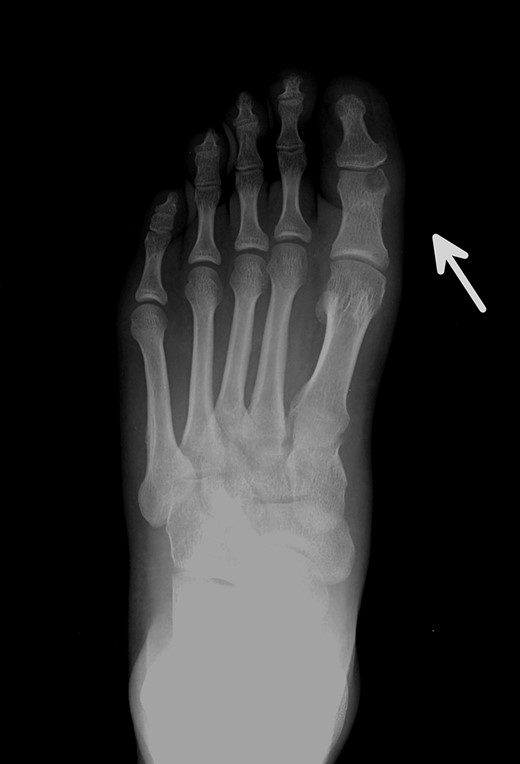

Posterior–anterior (A) and oblique (B) X-ray imaging of the left forefoot, showing the integration of the bone graft after 6 weeks.